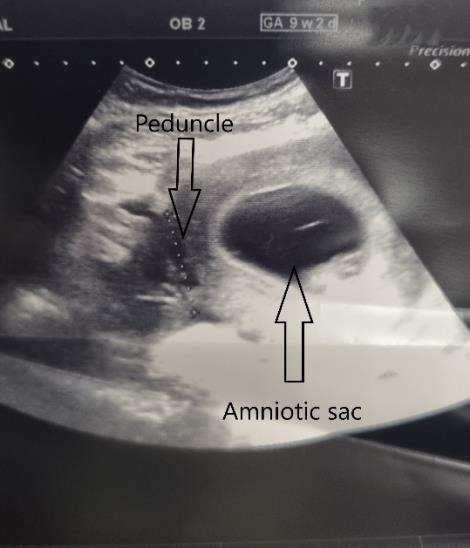

The management of symptomatic uterine fibroids during pregnancy is a challenging situation. In some cases, surgical therapy can be required. Reports indicate that both laparotomy and laparoscopy are safe methods. However, laparoscopy is associated with less morbidity. This paper describes the case of a 31-year-old woman with a symptomatic uterine fibroid which was removed by gasless laparoscopy.

Abstract Image